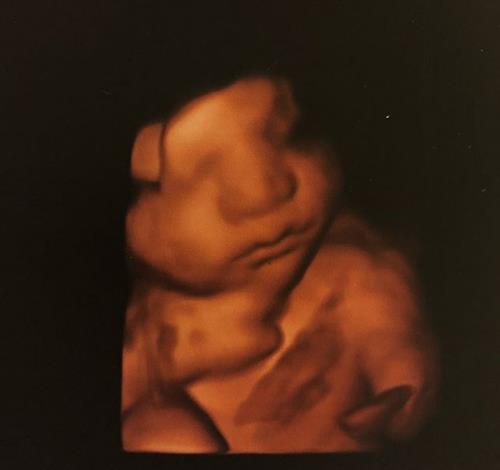

ថ្មីៗនេះ តារាសម្តែងវ័យ ៣៩ ឆ្នាំរូបនេះបានបង្ហោះរូបថតកូនប្រុសរបស់ខ្លួន ក្រោយឆ្លុះអេកូ ហើយក៏មានអ្នកគាំទ្រជាច្រើនចូលរួមត្រេកអរតាមរយៈពេលខមមិន នៅលើបណ្តាញសង្គមផងដែរ ៕